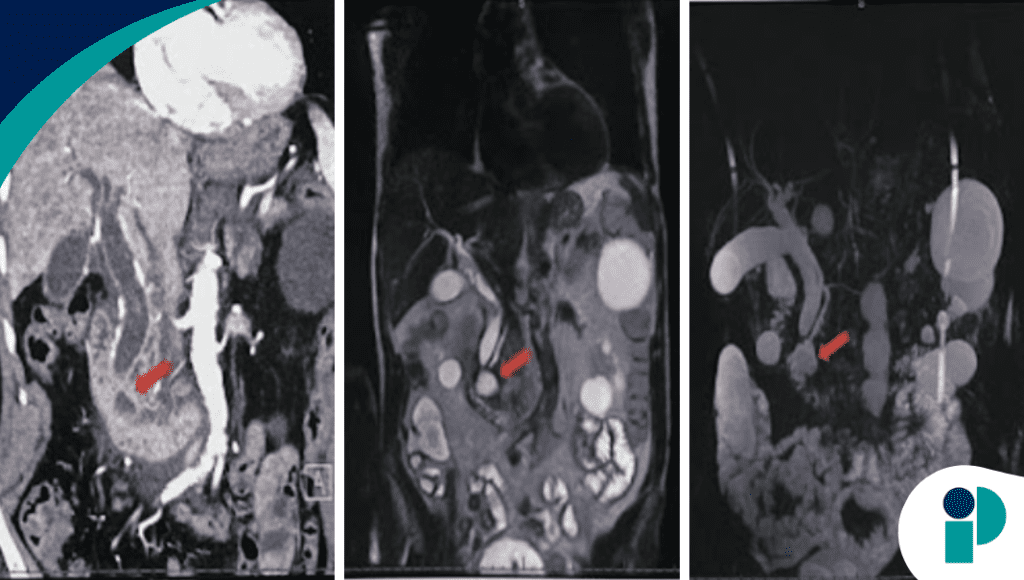

La tomografía abdominal evidenció inflamación pancreática con estriación de la grasa peripancreática, además de dilatación de la vía biliar y la presencia de un divertículo duodenal. Un hallazgo clave fue la ausencia de cálculos biliares en la ecografía, lo que obligó a ampliar el enfoque diagnóstico.

La colangiopancreatografía por resonancia magnética confirmó dilatación de la vía biliar sin defectos de llenado, junto con un divertículo periampular prominente, ubicado cerca de la ampolla de Vater. Este hallazgo permitió establecer el diagnóstico de síndrome de Lemmel, una entidad rara en la que el divertículo comprime estructuras biliares o pancreáticas, generando obstrucción.